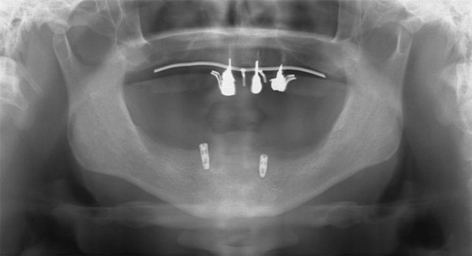

| | 下顎埋入後のデジタルパノラマです。3・3にインプラント体を埋入しています。 | 5/17 |

下顎右下3にボールアタッチメント、左下3にマグネット |

| | インプラント体がノーベル社の製品の場合、インプラント体はレギュラーネックのものしか使えません。角度が大きい場合(30度前後)、また骨の細い場合、NPのインプラント体を使用した場合はマグネットの高さが3ミリ以上になるのでかなり高くなりますから、マグネットよりも多少遊びが出ますがボールアタッチメントを選択します。 ちなみにインプラント体がストローマン社製ですと1.4ミリからマグネットがありますので高さにおける問題は出にくくなります。

両社製ともマグネット用にフラット・ドームという規格がありますが、角度がつく場合はドーム型を基本にします。下顎においてマグネットおよびボールアタッチメントのインプラント体の必要本数は2本のみです。 |